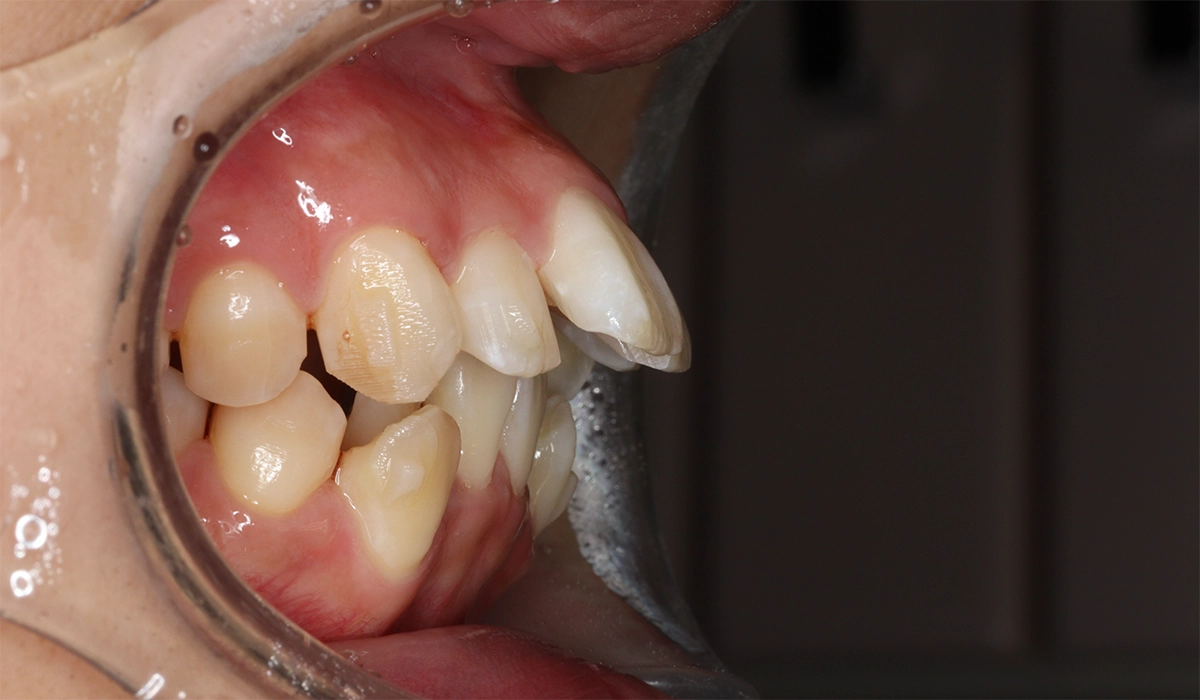

術前:右側